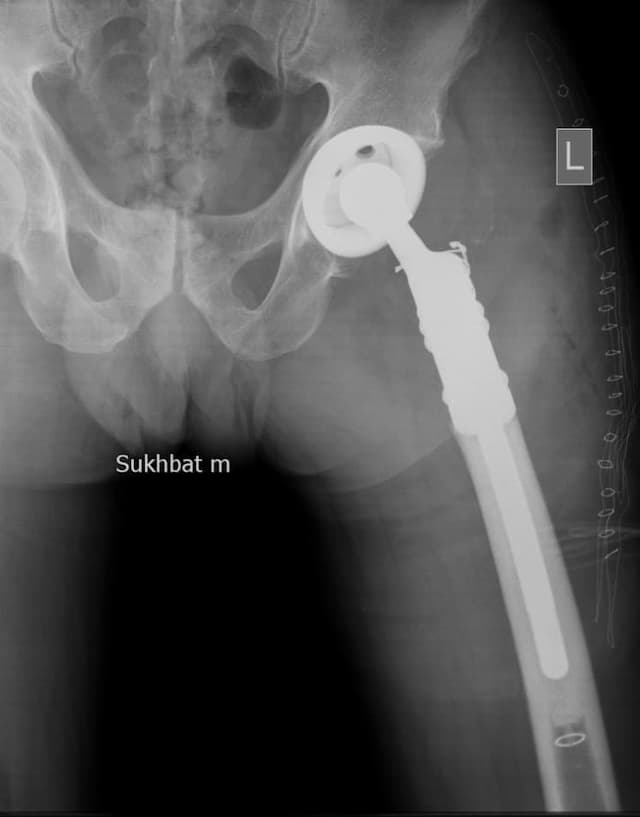

Мэс заслын өмнөх онош: Зүүн дунд чөмөгний түнхний үе орчмын ясны хавдар

Эсийн шинжилгээний хариу: Chondromyxoid fibroma

Шинж тэмдэг: Зүүн түнх, гуя орчим өвддөг, өвдөлт аажим ихсэж байсан, явах зогсох үед өвдөлт нэмэгддэг.

Хөдөлгөөний идэвх: Түнхний үеэр алцайх болон нугалах хөдөлгөөн бага зэрэг хязгаарлагдсан.

Хийгдсэн мэс заслын нэр: Дунд чөмөг-түнхний хавдрын хиймэл үе суулгах мэс засал. Эмнэлэгт хэвтсэн ор хоног 10.

Үе дайрсан ясны анхдагч хавдар, ясны дутмагшлын үед хийгдэх мэс засал image3

Зураг1. Зүүн дунд чөмөгний түнхний үе орчмын ясны хавдар